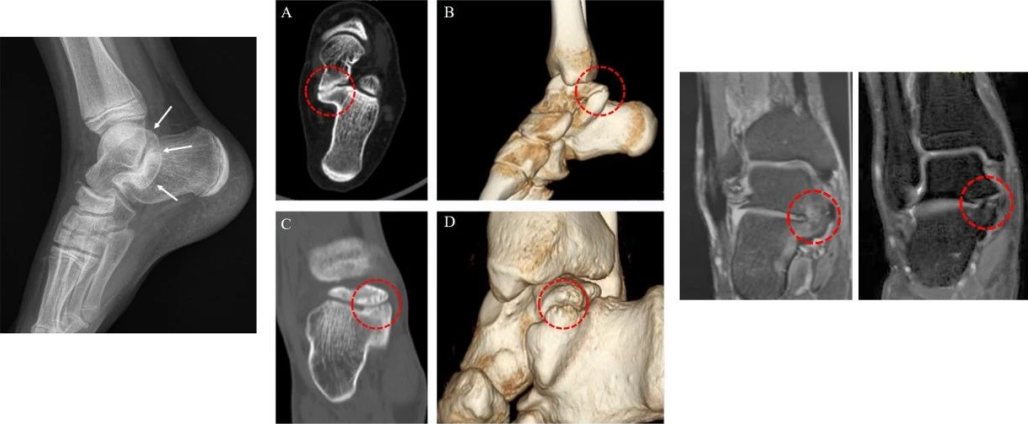

3D Printing – Guiding Talus Bridge Resection Surgery

Shortens surgery time, clarifies resection range, and reduces intraoperative fluoroscopy time.